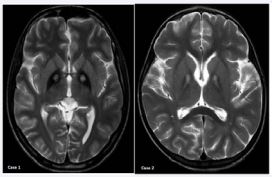

A 17-yr-old boy weighing 25 kg presented with a history of blepharospasm for 2 years, left-sided torticollis and opisthotonus for 6 months and was bed-bound in the past 3 months. MRI of the brain showed bilateral symmetrical, hyper intense signals with surrounding hypo intensities in the region of globuspallidus on T2 weighted images, consistent with the “eye of the tiger” sign. His dystonia remained refractory to medical management with trihexyphynydyl, tetrabenazine, carbamazepine, nitrazepam, clonazepam, syndopa (a combination of levodopa and carbidopa) and baclofen. Therefore, a pallidotomy was planned.

Figure 1 T2-weighted axial brain magnetic resonance images (MRIs) of both the cases shows the classical “eye of the tiger” sign in the globuspallidus.

A 5½-yr-old female child weighing 15 kilograms presented in acute dystonic crisis. She had abnormal movements initially in both the upper limbs, which progressed to involve lower limbs, trunk, head and neck over a period of 15 days. She also had difficulty in talking and breathing. On examination, the patient had generalized dystonia’s with intermit tent ophisthotonus and retrocollis. Her muscle tone was tough to evaluate because of pronounced rigidity. Predominant mouth breathing was present. The diagnosis was confirmed by an MRI of the brain that showed the “eye of the tiger” sign (Figure2a). Medical therapy with central anticholinergics, anticonvulsants and benzodiazepines failed therefore DBS was planned.